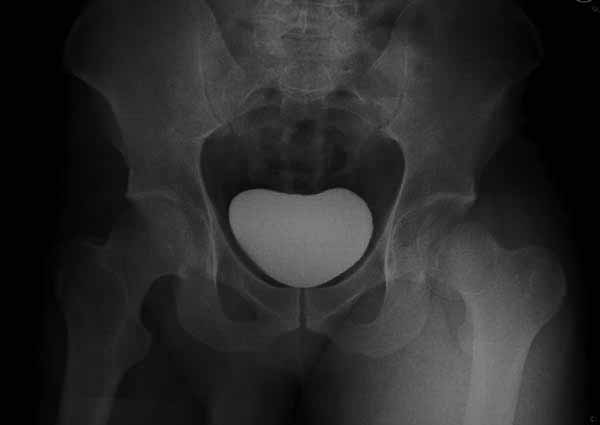

При сопутствующем переломе головки с ацетабулум, тогда артротомия из того доступа, который позволит фиксировать перелом впадины и фиксировать головку шурупами. На сегодня Headless Screw Synthes имеет преимущества перед другими, но при отстутствии их можно сделать обычными 3.5 мм., только головку надо утопить. При изолированном переломе доступ через trochanteric flip approach, который позволяет вывихнуть головку из ацетабулума и свободно работать без риска АВН. В вашем случае можно из переднего Smith Petersen доступа, потому что осколок спереди.

Представлены несколько вариантов фиксации: первый случай перелом головки с задним краем, операция из заднего доступа Кохер, а второй случай изолированный перелом головки - из трохантерного доступа.